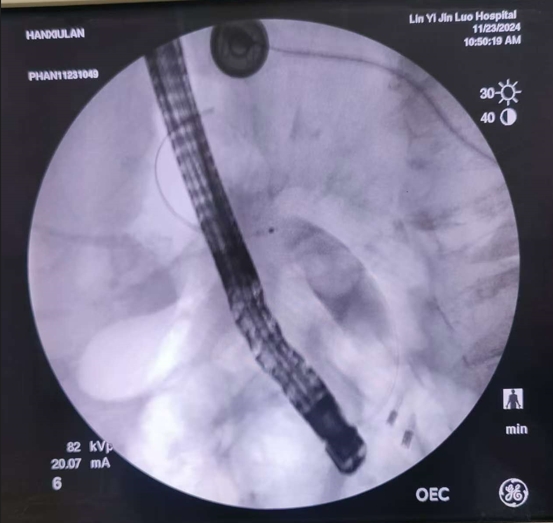

昨日在全程的精心监护下,为了做到更安全、万无一失,姜开通主任还邀请了市医院的曾宪忠主任共同参与,为老人实施了内镜下的逆行胆管造影治疗术,病人年龄超高,出现乳头处憩室,遇到困难,两位主任凭多年经验及超高手法,较为顺利给予病人做了微创治疗,术后老人的生命体征非常平稳,没有任何不适,今日查房患者和家属都感到非常满意和感激。